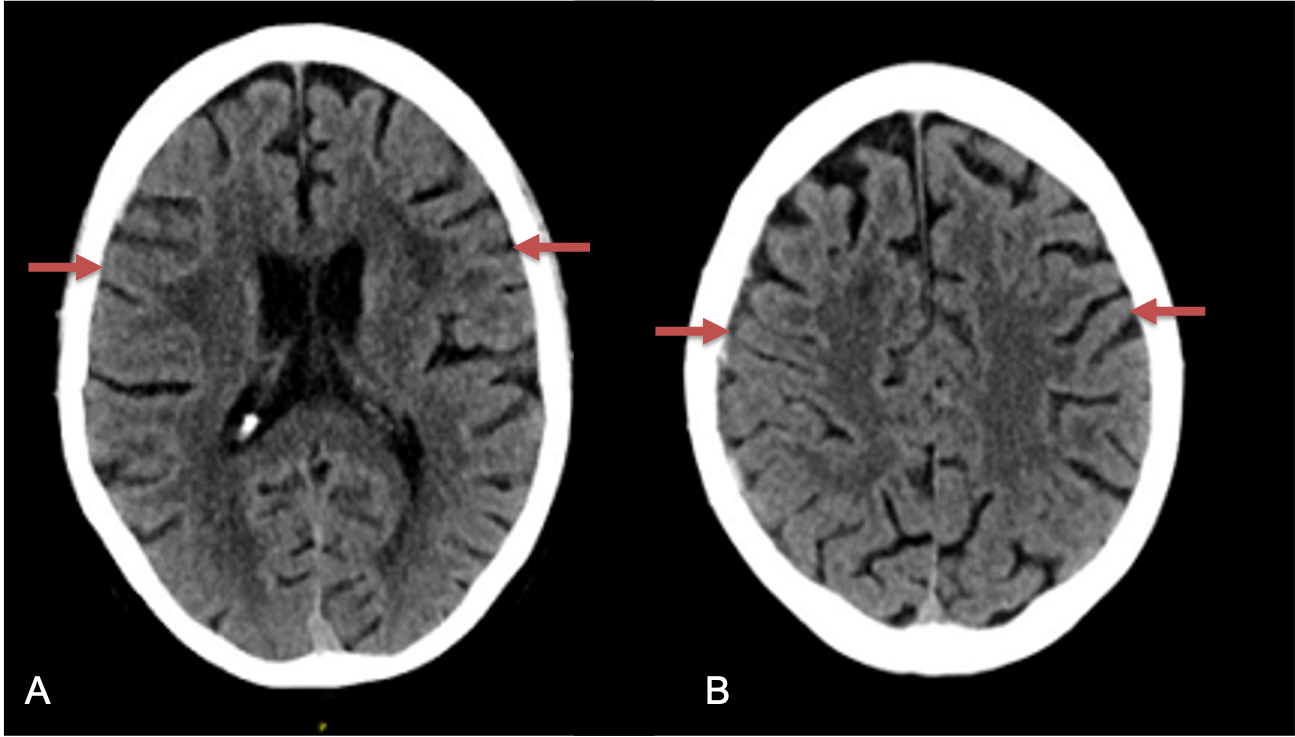

Clinically, the patient improved over the few weeks with the occasional transient twinge of a headache, but resolution of dizziness. Follow-up CT at 10 weeks demonstrated complete resolution of the bilateral subdural hematomas with our patient complete symptomatic and back to all of his activities of daily living. Considering his history of thrombocytopenia and CLL, we will continue to monitor him into the future and are excited about his progress and recovery. (Figure 4. A and B)

Figure 4. A and B) – 10 weeks following embolization demonstrates complete resolution of bilateral collections both acute and chronic.